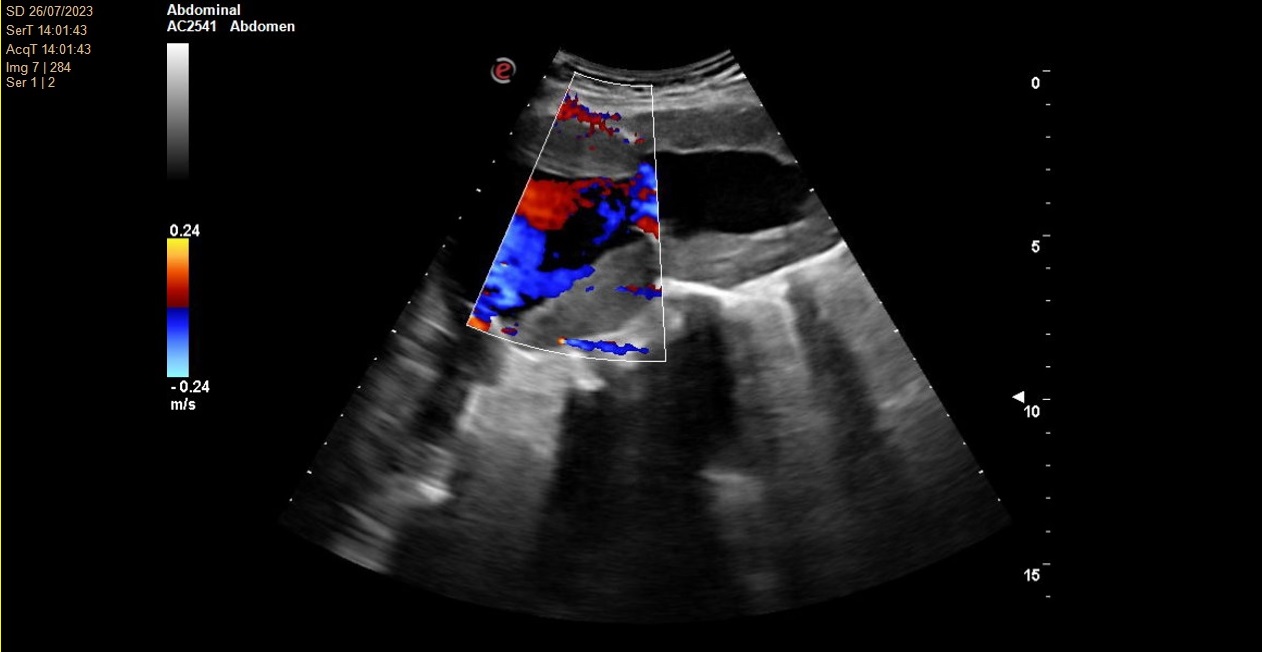

No se consigue visualizar el lóbulo hepático izquierdo ni páncreas por interposición de gas intestinal. Lóbulo hepático derecho de ecogenicidad y ecoestructura normal. Vesícula biliar de paredes finas y lisas sin contenido en su interior. Vía biliar no dilatada. Se visualiza una arteria aorta a nivel abdominal de un tamaño de 78 x 77 mm en su diámetro máximo.

Angio TC toracoabdominal en el que se observa una dilatación aneurismática de 73,8 mm de morfología fusiforme infrarenal hasta bifurcación ilíaca con trombosis mural concéntrica en toda su extensión.